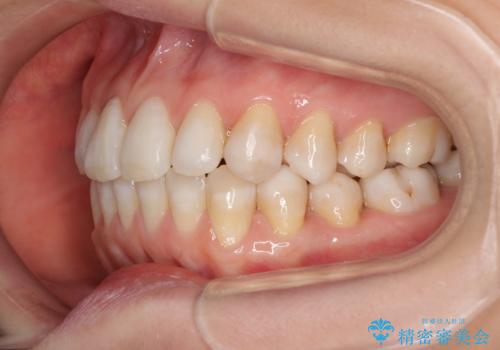

話しにくいオープンバイト インビザラインによる矯正治療

- 前歯の上下スペースによる話しにくさを気にして来院された患者様です。

インビザラインにより上下の前歯の隙間を閉じていくこととしました。

上下の奥歯を圧下させるようにすることで、前歯を接触させるように計画しました。

隙間に舌が入り込むことが話しにくさに繋がっていたため、舌の筋肉のトレーニングも並行して行い、話しにくさの改善と後戻りの抑制を図りました。